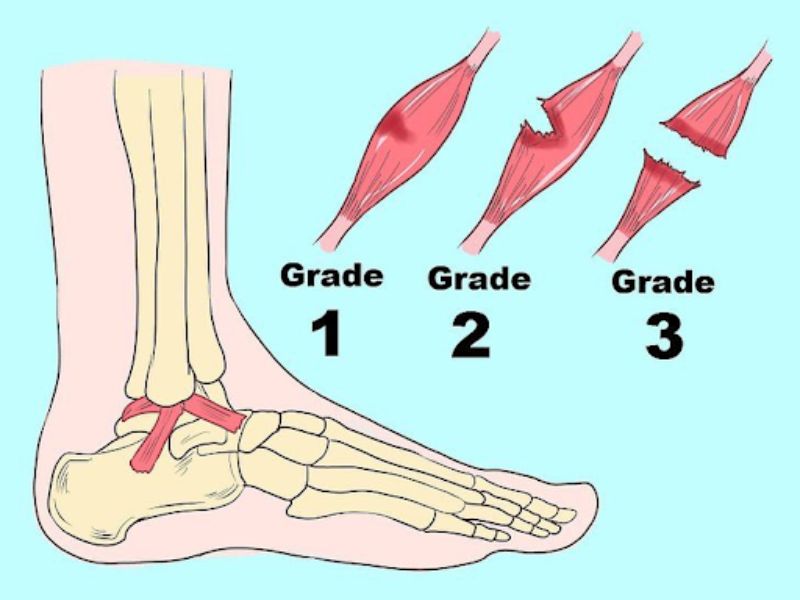

Lật sơ mi là gì? – Là tình trạng xảy ra khi dây chằng ở vùng cổ chân bị rách hoặc đứt thường gây ra các triệu chứng tương tự như bong gân. Thường xảy ra khi tham gia hoạt động thể thao hoặc vận động mạnh. Chấn thương này thường xuất hiện khi vận động không đúng cách hoặc có tác động đột ngột làm chân không kịp thích nghi. Các dấu hiệu như sưng đỏ, vết bầm tím và đau đớn kéo dài, cùng với sự hạn chế vận động và sưng phù là những điểm nhận biết rõ ràng của lật sơ mi. Giờ thì bạn đã biết lật sơ mi là gì rồi.

- Chấn thương bên trong xảy ra khi các dây chằng bên ngoài bị đứt trước. Sau đó, các dây chằng ở cấp độ 2 và cấp độ 3 có thể làm cho khớp trở nên không ổn định, gây tổn thương nghiêm trọng hơn. Thường đi kèm với tổn thương dây chằng hoặc gãy xương.

- Chấn thương bên ngoài xảy ra khi các dây chằng bên trong chịu áp lực tác động mạnh, gây đứt và có thể bị xoay ra ngoài, tạo lực ở khớp bên ngoài. Lực này có thể gây gãy xương và đứt dây chằng. Trong trường hợp nghiêm trọng hơn, có thể làm cho khớp mất tính ổn định.